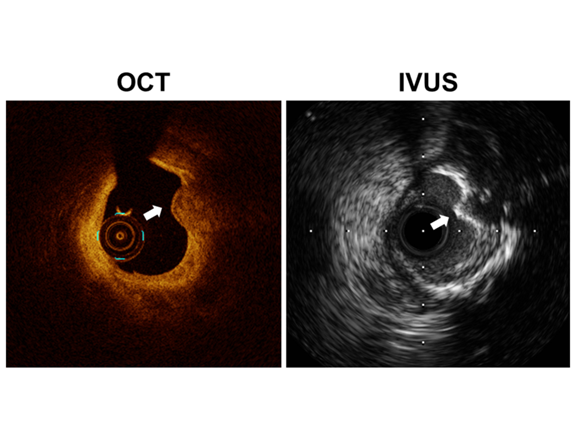

Q) CNをIVUSでなくOCTで観察することの意義は、どのようなところにありますでしょうか。またCNを血管内イメージングで観察する際のポイントを教えてください。

A) IVUSは石灰化の有無については大変優れていますが、CNに関してはOCTと比べて過大評価する可能性があります。今回我々のCNの定義において、”内腔に突出するnodular calcification” の所見が最も重要なのですが、IVUSでは”nodular calcification” の診断能が不十分のため、“突出した石灰化病変”のみでCNと診断する可能性があります。

観察に際しては、①石灰化のシート(calcium sheet)に連続し、②突出する病変で、③小さい粒状のnodular calcificationが表面に見られることがポイントです。